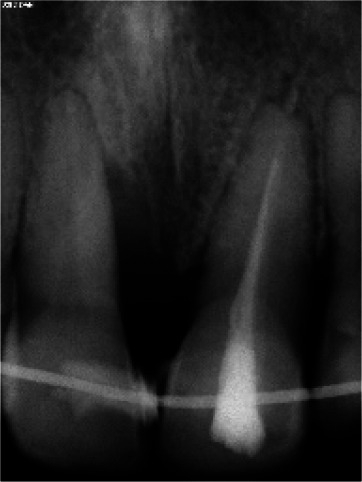

This case report exhibits a heavy smoker female patient with a localized stage III periodontitis who has been under the smoking cessation program during the pre-surgical period, followed by a strict maintenance program for the past twelve years, after being treated with guided tissue regeneration techniques and restored with zirconia prosthetic crowns. A 50-year-old, heavy smoker (> 40 cigarettes per day), systemically healthy female patient presented complaining of mobility and pain in the upper right central incisor, which was temporarily splinted to the left central incisor using resin composite. After clinical and radiographic examination, significant damage of the attachment apparatus, deep periodontal lesions extending the middle portion of the root, and severe infrabony defect were noted. Following the initial hygienic phase, a guided tissue regeneration surgery using xenograft bone substitute covered by a resorbable collagen membrane was performed. After six months of healing, four zirconia crowns were cemented on the central and lateral incisors based on patient esthetic compliance. During the 12-year follow-up period, neither residual pockets nor gingival recession were observed, and perfect marginal bone stability, and esthetic and functional results were noted. This case shows the predictability of a conservative surgical technique, the guided tissue regeneration, based on appropriate treatment planning and a strict maintenance program. It also demonstrates the importance of at least a 6-month healing period after such surgeries, allowing complete tissue maturation and a re-establishment of the supra osseous gingival tissues in order to locate the prosthetic margins without interfering with the soft tissues integrity.